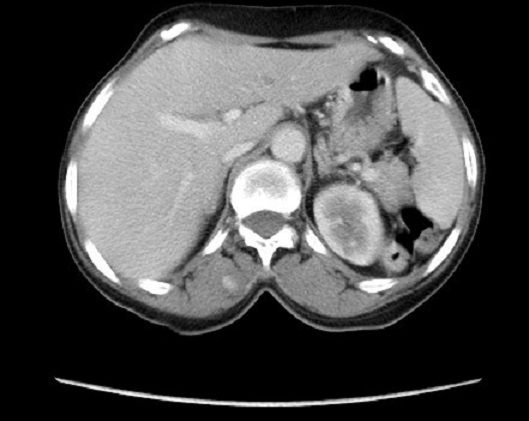

La maladie de Kaposi est une maladie angioproliferative multifocale, dont les localisations cutanéo-muqueuses sont les plus fréquentes. Nous en rapportons un cas avec une atteinte musculo squelettique. Patiente de 55 ans, présente depuis un an de multiples nodules angiomateux confluents en des tumeurs ulcéro bourgeonnantes sur un placard hyperpigmenté et œdème de la jambe gauche, associés à des macules angiomateuses de la plante du pied droit. La biopsie cutanée était en faveur d’une maladie de kaposi, la sérologie VIH était négative. Le bilan lésionnel objectivait une lyse du premier et du deuxième métatarsien, des micronodules parenchymateux pulmonaires bilatéraux, des adénopathies pré trachéales, et une lésion musculaire para vertébrale de 3cm prenant fortement le contraste. L’atteinte du système musculo-squelettique dans la maladie de Kaposi est très rare, seulement 66 cas publiés dans la littérature, dont 3 uniquement comprenaient une atteinte musculaire, avec une sérologie VIH positive. Les lésions osseuses étaient les plus fréquentes. Les patients étaient rarement asymptomatiques, presque tous les patients avaient des lésions concomitantes non osseuses. Chez notre patiente, il s’agit d’une maladie de Kaposi classique avec une atteinte multifocale: cutanée, pulmonaire, ganglionnaire, osseuse par contigüité et musculaire para vertébrale sans atteinte cutanée en regard, ce qui fait la particularité de notre observation. Un traitement à base d’une chimiothérapie était instauré avec une bonne réponse. L’atteinte du système musculo squelettique bien qu’elle est rarissime, son exploration n’est pas systématique tant qu’elle est asymptomatique, sa prise en charge rejoint celle de la maladie de kaposi.